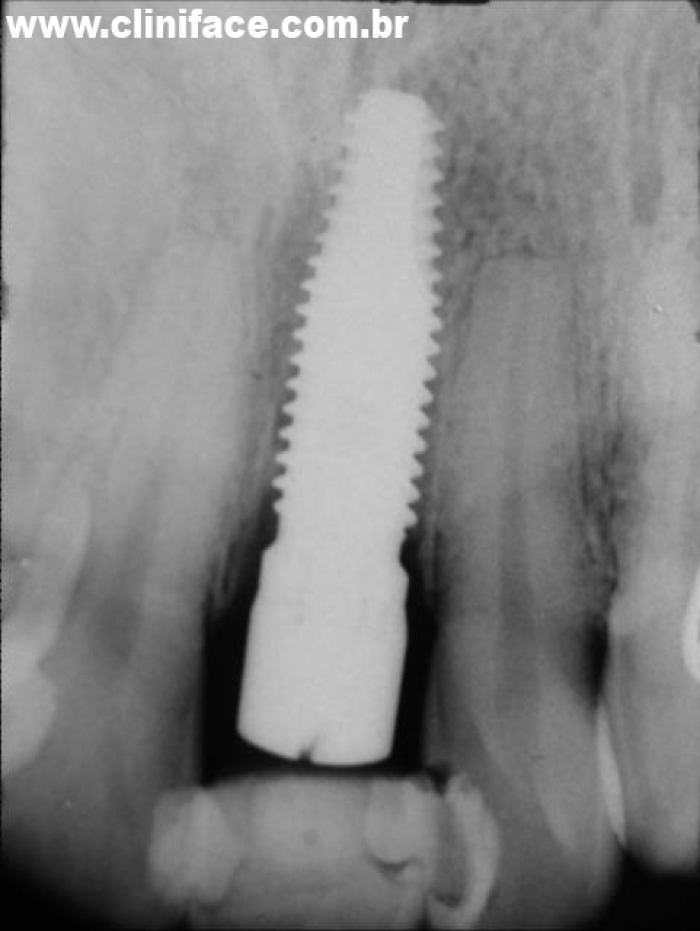

Raio X do implante instalado